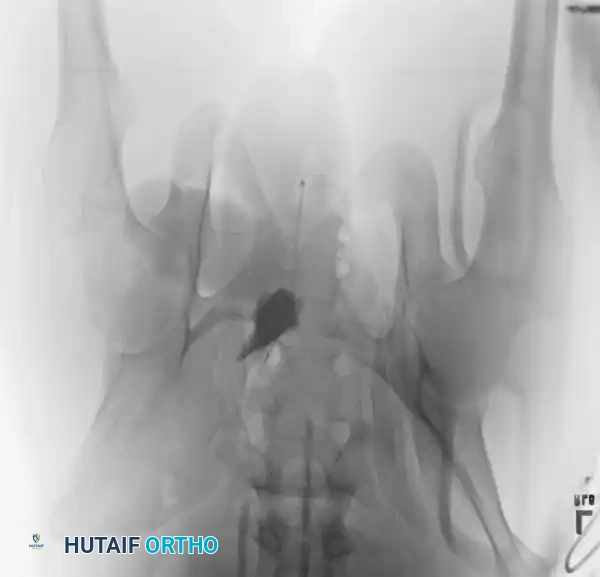

Surgical Indications and Timing

Operative intervention is indicated for:

1. Symphyseal diastasis > 2.5 cm (APC II/III).

2. Vertical instability (Tile C / VS).

3. Severe rotational deformity causing leg length discrepancy or internal organ impingement (severe LC injuries).

4. Open fractures requiring debridement and stabilization.

Timing: Damage control orthopedics (external fixation, pelvic packing) is performed immediately. Definitive Open Reduction and Internal Fixation (ORIF) is typically delayed 5-10 days to allow for hemodynamic optimization and resolution of the initial inflammatory hit, provided the patient is physiologically stable.